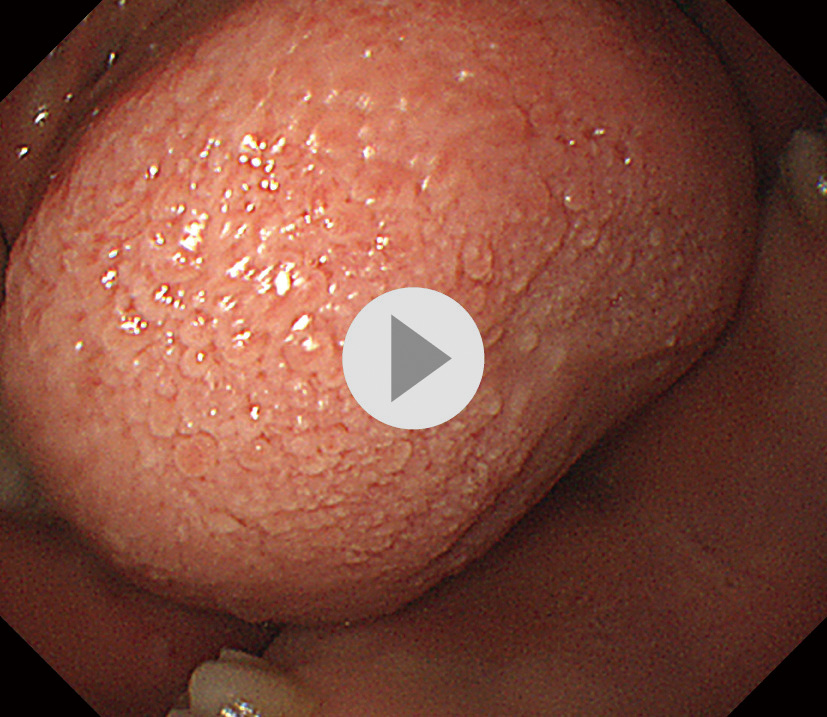

【症例1】40歳代,女性.

主訴:胃痛,むかつき,呑酸,咽頭違和感

既往歴など:10年前に胃ポリープを指摘された.H. pyloriの除菌歴なし.非喫煙,非飲酒.

悪性腫瘍の家族歴:なし

内服歴:なし

内視鏡検査法:鎮痙剤・鎮静剤なし,炭酸ガス送気使用,経口挿入.IEE (NBI) 併用.

使用機種:GIF–P260 (オリンパス,面順次方式電子内視鏡)

検査場所:増山胃腸科クリニック (大田原市,増山仁徳院長)

内視鏡画像:ⓔ動画11-1-4 (134枚の静止画を連続再生) 参照

内視鏡検査所見・診断:report (図1) 参照

検査時間:12分

撮影枚数:134枚

生検結果:Group 1 fundic gland polyp